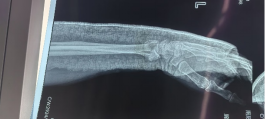

安裝外架

術后外觀及影像

患者男性,54歲,外傷致右側脛腓骨開放性骨折8小時,局部可見右側脛骨骨折近端露出···